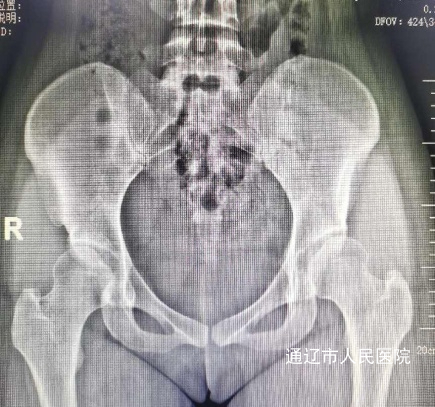

术前影像:

患者张某,女性,24岁,2年前开始出现左侧髋关节肿痛伴活动受限,严重影响日常生活,门诊经过查体及髋关节半髋磁共振检查诊断为:髋臼撞击综合征合并盂唇撕裂。由于患者年纪较轻,左侧髋关节撞击导致髋臼盂唇损伤,长期疼痛,胡中申主任医师带领其关节外科团队对该病例进行详细周全地讨论,综合评估患者病情并得到家属同意后,建议实施髋关节镜手术治疗。